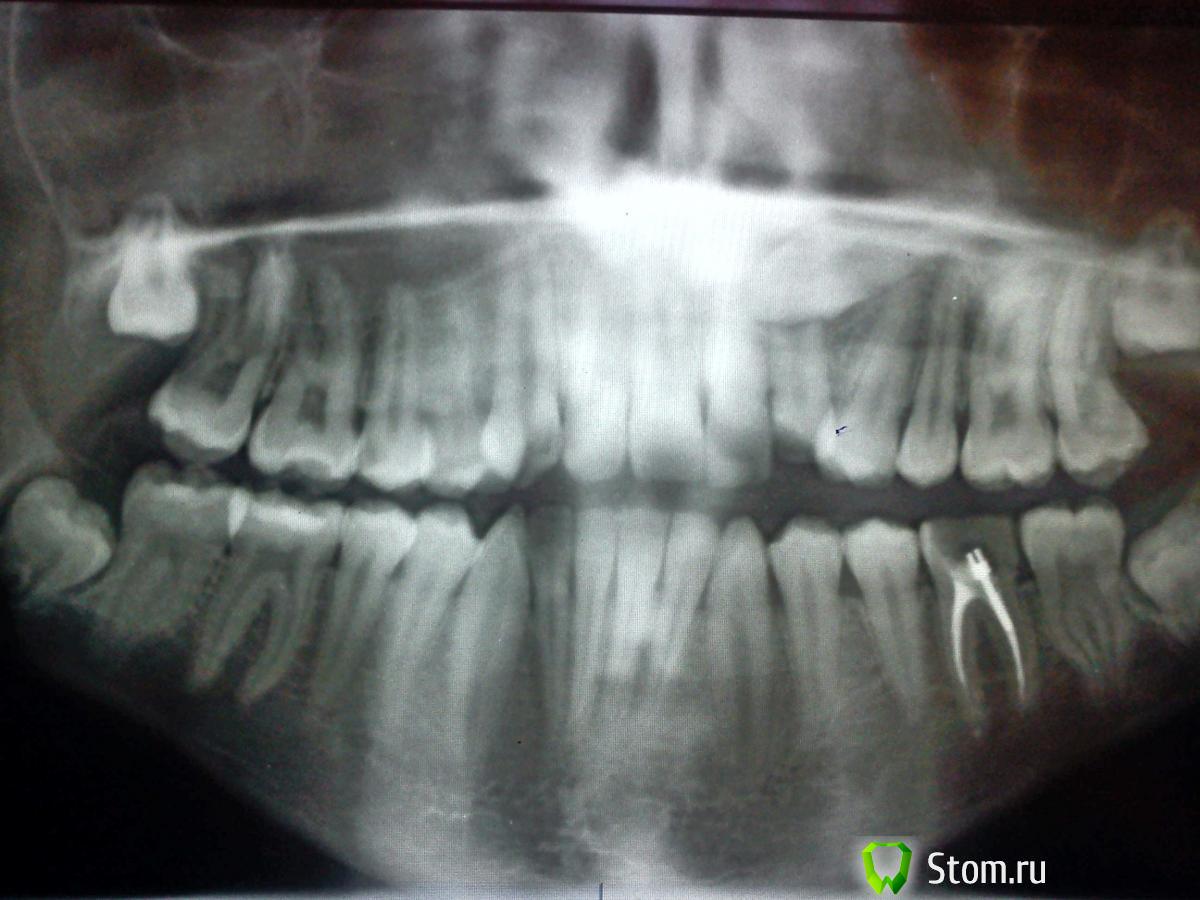

Здравствуйте, хотелось бы узнать ваше мнение по моему случаю, у нас в городе всего 2 ортодонта, поэтому не с кем сравнивать мнения...Возможно ли вытянуть верхний клык(находится чуть правее середины верхней челюсти если что)? и высока ли вероятность успешного вытягивания? и в итоге челюсть верхняя станет нормальной, шире т.е.?post-27116-0-06863100-1331627193_thumb.jpgpost-27116-0-84361200-1331627177_thumb.jpg